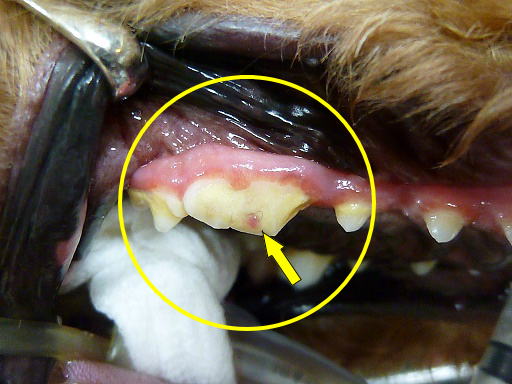

破折した第4前臼歯

今回、抜髄を行う第4前臼歯です。

露髄し、出血点が確認できます。